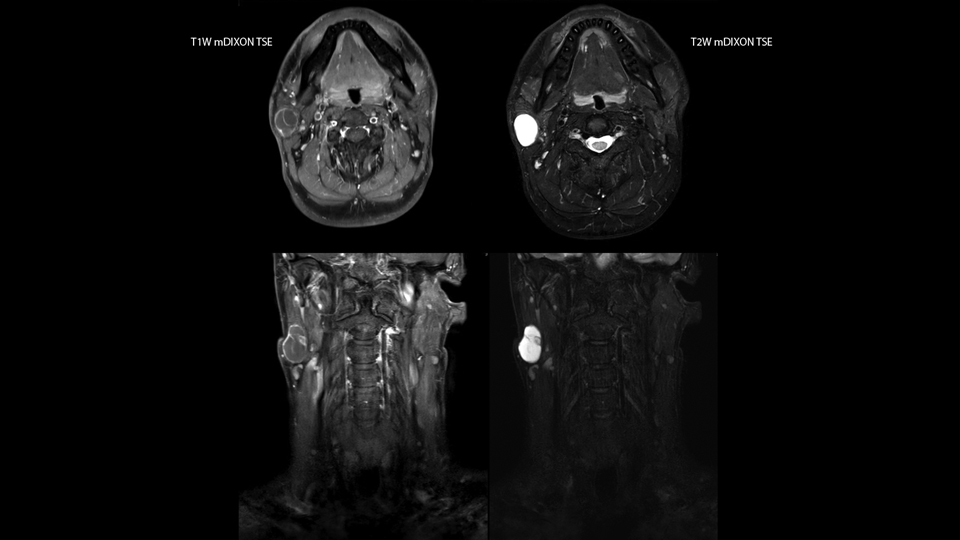

“Our DMG Lisle location includes a cancer center, so soft tissue neck scans, brachial plexus scans, and prostate scans are common. For these exams, mDIXON TSE provides excellent images with and without fat suppression all while helping us reduce repeats and work more efficiently,” Mr. Duffy says.

“With the 2-echo Philips mDIXON TSE the timing is short and the fatsat is very robust. The biggest thing is that you know your fat suppression will be good, even in thin patients or large patients that are off-center,” Mr. Sybesma says.

“Since we work in fixed time slots, not having to repeat scans is key for us,” Mr. Duffy adds. “With mDIXON TSE we get high quality results the first time – unless of course the patient absolutely jumps off the table. For us, that’s significant, because just a single repeat scan could put us behind schedule.

“mDIXON TSE raises our diagnostic confidence with its homogeneous

fat suppression. Neck exams and rheumatology patients are two examples where mDIXON TSE is especially useful,” Dr. Kaakaji says. “For us it’s also an efficiency boost in exams where we need pre and post T1-weighted images with great fat suppression.”